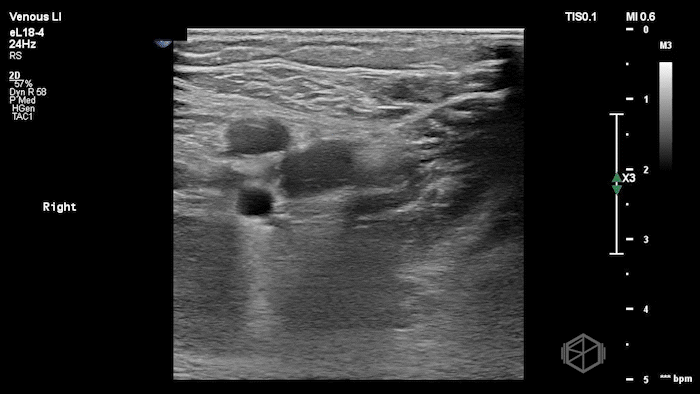

A lower extremity DVT ultrasound performed by Dr. Koutsounadis demonstrated the following:

The POCUS shows a right common femoral vein thrombus. Family members reported that the patient had previously been diagnosed with a DVT very recently and was on apixaban.

The thrombus appeared predominantly hypoechoic to nearly anechoic, making it difficult to appreciate on B-mode imaging alone. However, incomplete compressibility of the vein confirmed the presence of thrombus.

Diagnosis: Right common femoral partially occlusive DVT